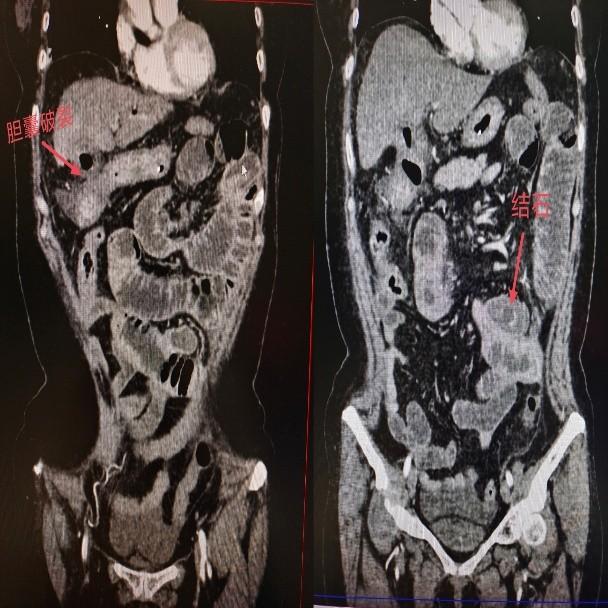

普外科周亮主任接诊后,通过腹部CT检查确诊:李阿姨的胆囊已发生穿孔,一枚结石从破口处掉入小肠并嵌顿,形成机械性肠梗阻,局部肠壁已出现明显水肿、炎症。考虑到患者年龄较大、病情复杂,医生先尝试保守治疗,但经过一周的禁食、胃肠减压、抗感染等措施后,结石仍未排出,肠梗阻症状持续存在。

为避免病情进一步恶化,周亮主任团队与家属充分沟通后,制定了“分步处理、先急后缓”的手术方案。12月16日,医生为李阿姨实施小肠切开取石术,成功取出三枚结石,其中最大的一枚直径约5厘米,呈鸡蛋大小。术后,李阿姨腹痛症状迅速缓解,在医护团队的精心照料下恢复良好,已顺利出院。周亮主任表示,待患者身体完全康复后,还需择期进行胆囊切除术,从根源上避免结石复发。